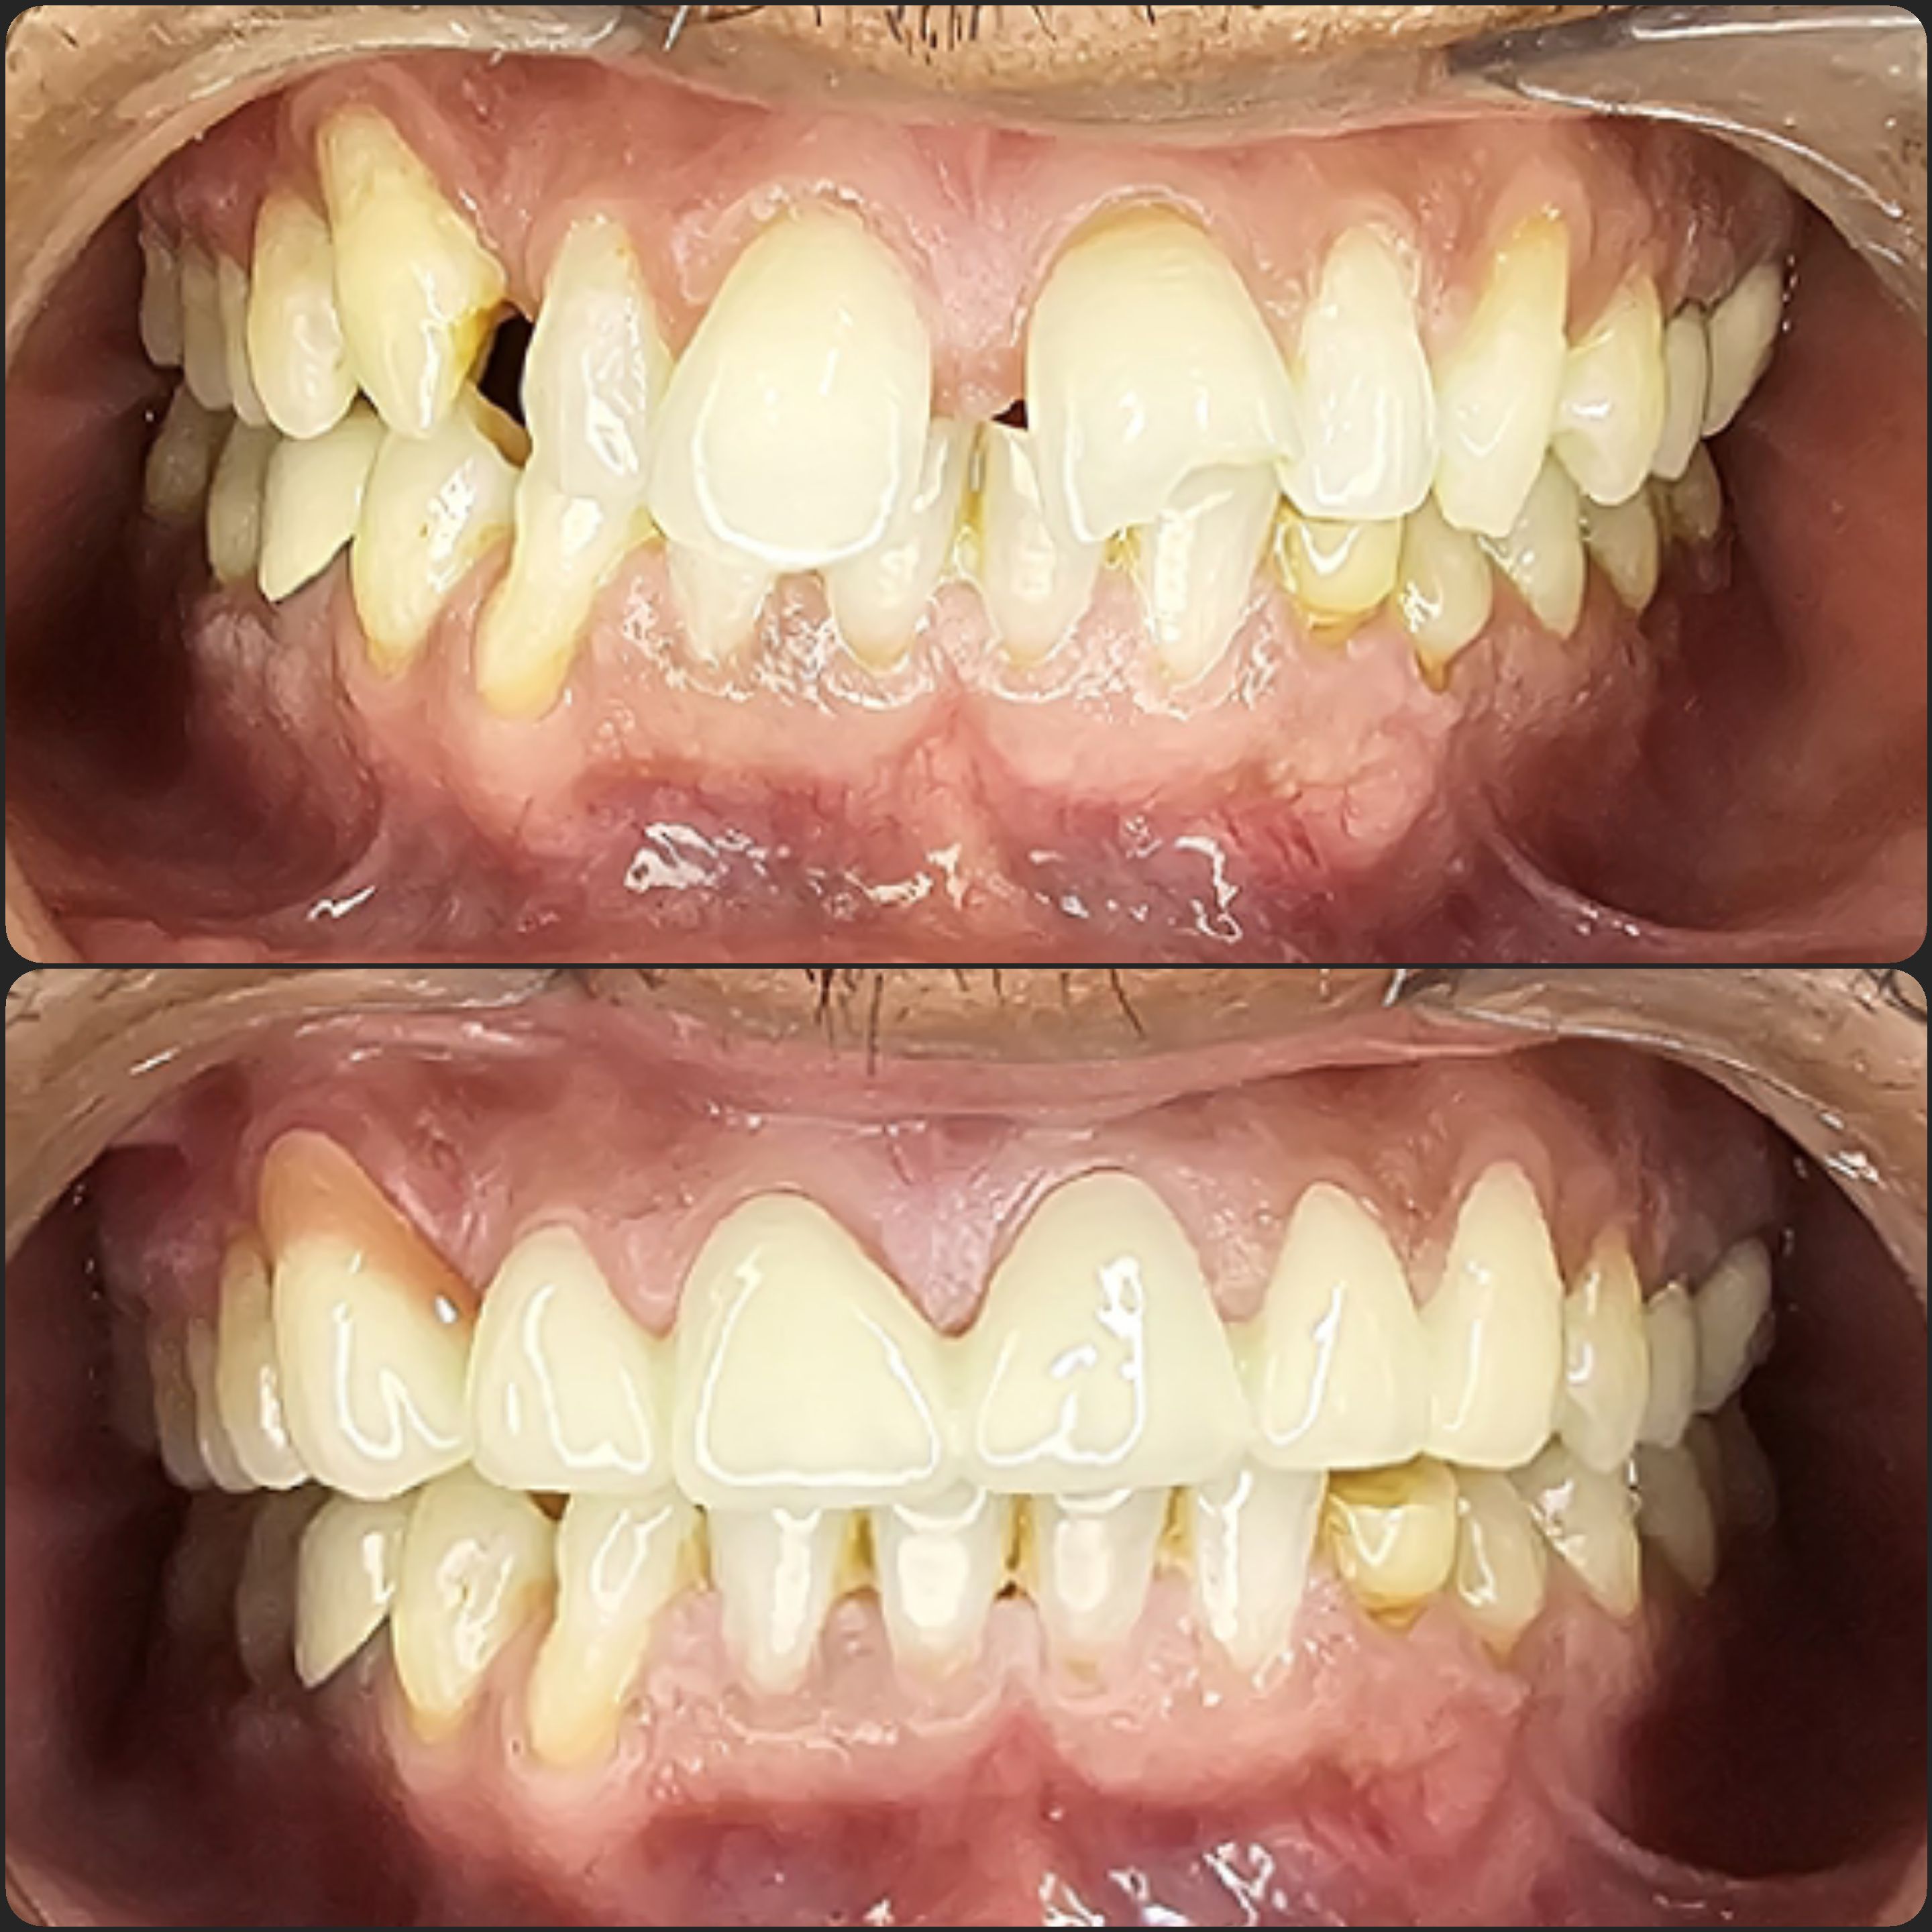

Cases